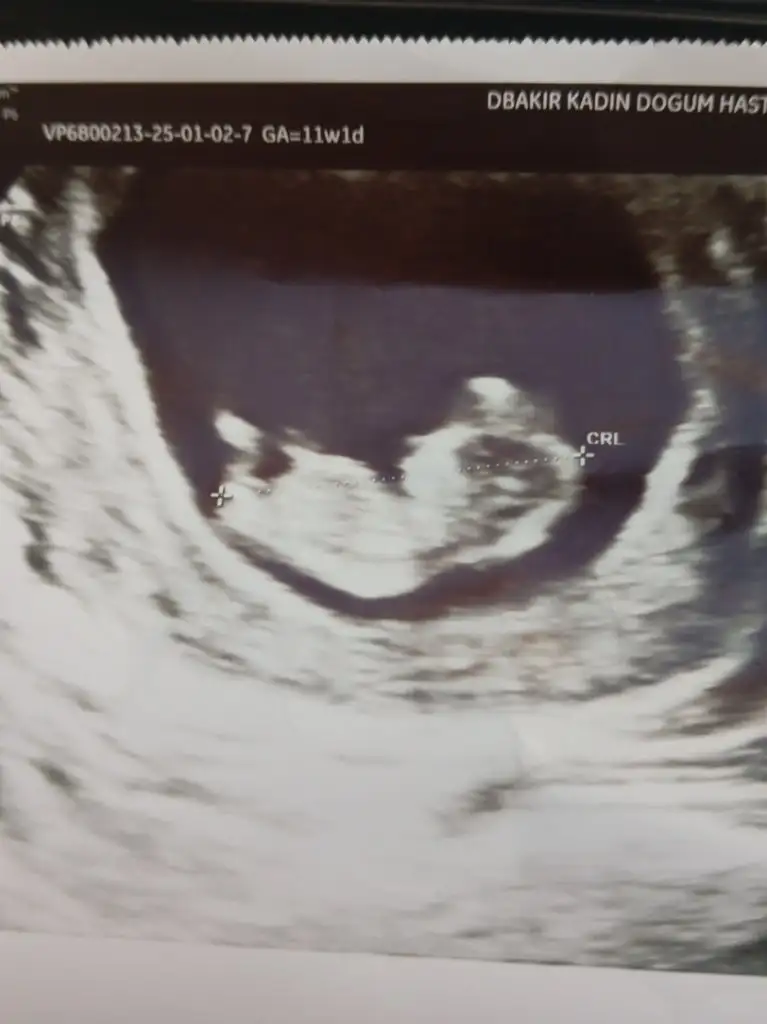

Sizin bebeğe de erkek diyor chat gpt.

Benim bebeğime de 7 haftalikken erkek demişti, 11 haftalikken yine erkek dedi. Sonra fetal dna sonucu çıktı gercekten erkekmis :)

Ekran görüntüsünü asagida iletiyorum